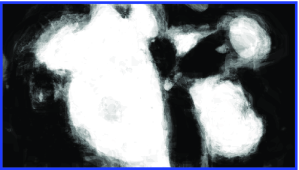

Appearance is one of the most important visual cues to distinguish between different structures in an image. Appearance is described by studying the distribution of different features such as intensity values in gray-scale images, color, and texture inside each object. In most cases, appearance models are incorporated into the data term in (2) and (7). The purpose of incorporating appearance prior is to fit the appearance distribution of the segmented objects to the distribution of objects of interest, e.g. using Gaussian mixture model (GMM) (Rother et al., 2004). In the literature, there are two ways to model the appearance: 1) adaptively learning the appearance during the segmentation procedure, and 2) knowing the appearance model prior to performing segmentation (e.g. by observing the appearance distribution of the training data). In the former case, the appearance model is learned as the segmentation is performed (Vese and Chan, 2002) (computed online). In the second case, it is assumed that the probability of each pixel belonging to particular label is known, i.e. if represents a particular set of feature values (e.g. intensity/color) associated with each image location for object, then it is assumed that is known (or pre-computed offline). This probability is usually learned and estimated from the distribution of features inside small samples of each object. Figure 9 illustrates the probability of different structures (the kidney, the tumour, and the background) in an endoscopic scene. A lower intensity in Figures 9(b-d) corresponds to higher probability.